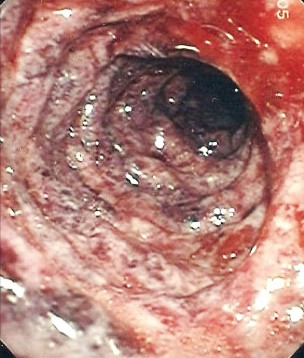

Гигантские язвы дуоденум (рис. 3) (более 2 см) также имеют высокую частоту осложнений, включая кровотечение, пенетрацию и перфорацию. Верхняя эндоскопия имеет преимущества в диагностике гигантских язв желудка перед рентгенологическим исследованием. Могут быть пропущены гигантские язвы дуоденум, которые из-за больших размеров можно принять за луковицу двенадцатиперстной кишки, псевдодивертикул или истинный дивертикул луковицы дуоденум. Эндоскопия также важна для исключения злокачественности и редких причин гигантских язв, в том числе болезни Крона, эозинофильного гастроэнтерита, ишемии, может потребоваться для лечения осложнений, ассоциированных с гигантскими размерами. Данной категории пациентов необходимы контрольные эндоскопии для документирования заживления, основанные на повышенной частоте осложнений, связанных

с такой патологией.